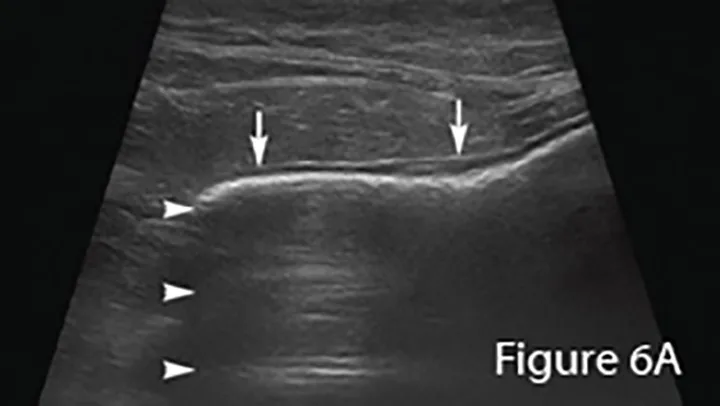

Ultrasound image of an enlarged intestine (arrows) showing large amount of reverberation artifact (arrowheads) caused by luminal gas. This prohibits visualization of the far wall of this loop of bowel. The ultrasound impression was a distended colon.